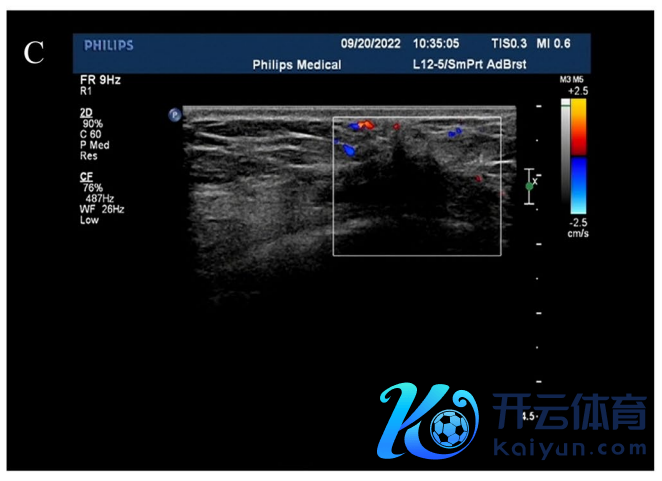

超声诊断:右乳肿块,BIRADS-US分级:4C级。右腋窝淋凑趣儿肿大(图1B,C)。

图1B,C. 乳腺超声示右乳7点乳头旁约2.1 cm×1.0 cm低回声团,神志怪异正,边界不清,内有点状强回声,CDFI:可见血流信号。